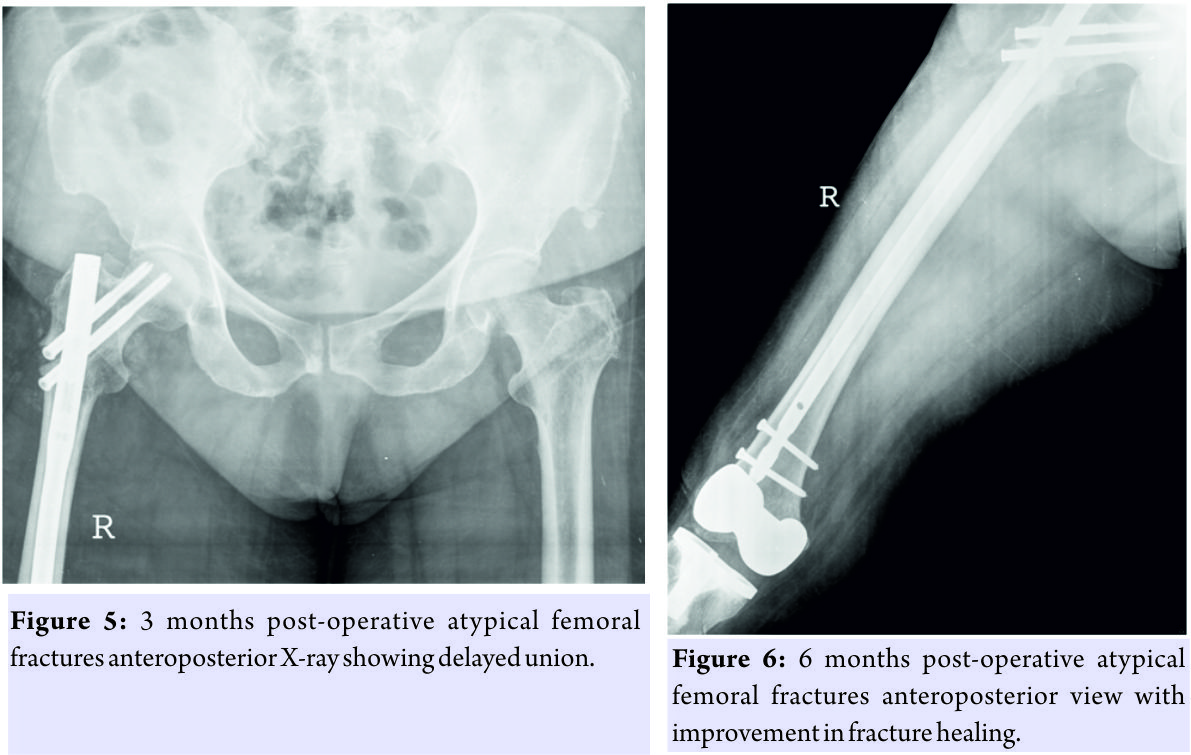

This was treated by way of sequestrectomy and saucerization in January 2013 (Fig. 2) and stoppage of Alendronate. There was no history of the patient having any dental procedure while on alendronate. In March 2013, she was admitted with complaints of pain and swelling over the right thigh following a history of trivial fall, and after clinical examination and history taking, X-rays were done which showed an atypical right displaced subtrochanteric fracture through the focally thickened lateral cortex of proximal femur (Fig. 3). The fracture was managed surgically with proximal femoral nailing (Fig. 4). The knee replacement was unrelated to the sub-trochanteric fracture. For the subtrochanteric fracture of femur, regular follow-ups were done postoperatively with serial X-rays. Blood investigations were done, and serum calcium was 9.5mg/dl, and serum Vitamin D3 was 20ng/ml which was optimized with 6,00,000 IU of intramuscular Vitamin D3 and maintained by oral Vitamin D3 medications. At 3 months, the fracture was in delayed union (Fig. 5),and hence, the patient was started on injection Teriparatide 20mcg subcutaneous for a period of 18 months. The patient was kept non-weight bearing. The 6 months X-ray showed further progression in fracture healing (Fig. 6),and the patient was allowed partial weight bearing. In October 2013, 10 months after stopping Alendronate, she again came with the complaint of pain in the right side of the jaw; X-rays showed relapse of ONJ (Fig. 7) sequestrectomy was done on the right mandible. In February 2014, 13 months after stopping Alendronate, the patient came with the increased pain of the right mandible and was diagnosed as a fracture of the right mandible; the fracture was operated on and fixed with a plate in February 2014 (Fig.8).

The knee replacement was unrelated to the sub-trochanteric fracture. For the subtrochanteric fracture of femur, regular follow-ups were done postoperatively with serial X-rays. Blood investigations were done, and serum calcium was 9.5mg/dl, and serum Vitamin D3 was 20ng/ml which was optimized with 6,00,000 IU of intramuscular Vitamin D3 and maintained by oral Vitamin D3 medications. At 3 months, the fracture was in delayed union (Fig. 5),and hence, the patient was started on injection Teriparatide 20mcg subcutaneous for a period of 18 months. The patient was kept non-weight bearing. The 6 months X-ray showed further progression in fracture healing (Fig. 6),and the patient was allowed partial weight bearing. In October 2013, 10 months after stopping Alendronate, she again came with the complaint of pain in the right side of the jaw; X-rays showed relapse of ONJ (Fig. 7) sequestrectomy was done on the right mandible. In February 2014, 13 months after stopping Alendronate, the patient came with the increased pain of the right mandible and was diagnosed as a fracture of the right mandible; the fracture was operated on and fixed with a plate in February 2014 (Fig.8). Meanwhile, the patient continued injection Teriparatide. At 1year postoperatively, the atypical femoral subtrochanteric fracture had healed (Fig. 9) and the patient was allowed full weight bearing. 24 months postoperatively, X-rays confirmed solid union of the atypical subtrochanteric femoral fracture (Fig.10). On recent review, the patient walks full weight bearing without the need of any support, with a normal gait and is completely asymptomatic as regards the femur as well as the jaw.